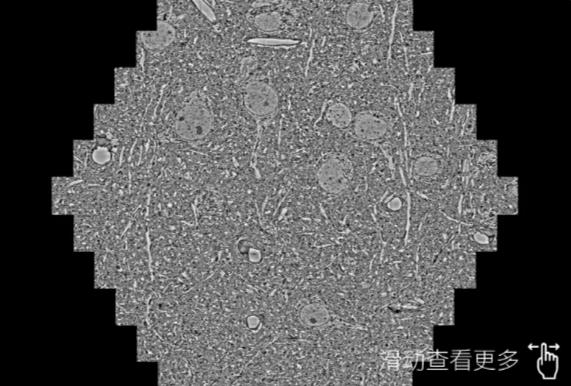

鼠脑切片。左图使用天水蔡司天水扫描电镜MultiSEM706对165μmx143pm面积区域成像,耗时仅需1.5秒。右图为鼠脑切片中30μm区域放大效果。样品由芝加哥大学B.Kasthuri提供。

使用蔡司高速天水扫描电镜MultiSEM对1mm²人脑皮层组织进行高分辨成像,并对其中的各种细胞结构进行三维重构分析。左图展示了2x3mm²组织平面中锥体神经元的三维重构效果。右图显示了局部体积神经元三维重构。图像由哈佛大学chtman实验室提供,渲染图由D. Berger 制作。